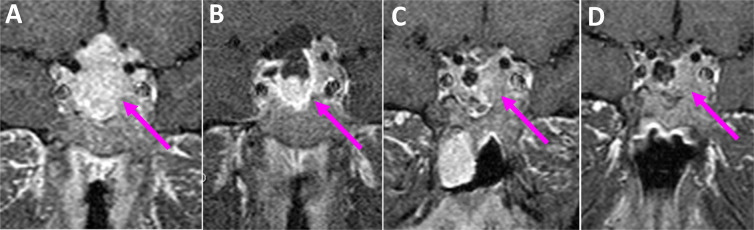

Methods: A total of 28 patients with pituitary adenoma were evaluated. All patients did four sellar MRIs. The first MRI was done before surgery, and three were done 48 hours, two weeks, and three months after the surgery. Finally, the MRI findings at different times were compared to each other.

Results: The pituitary gland and adenoma signals were constant at all time points. The signal of the packing material showed no differences in T1-weighted and T1-weighted with contrast sequences but showed changes in T2-weighted sequences.